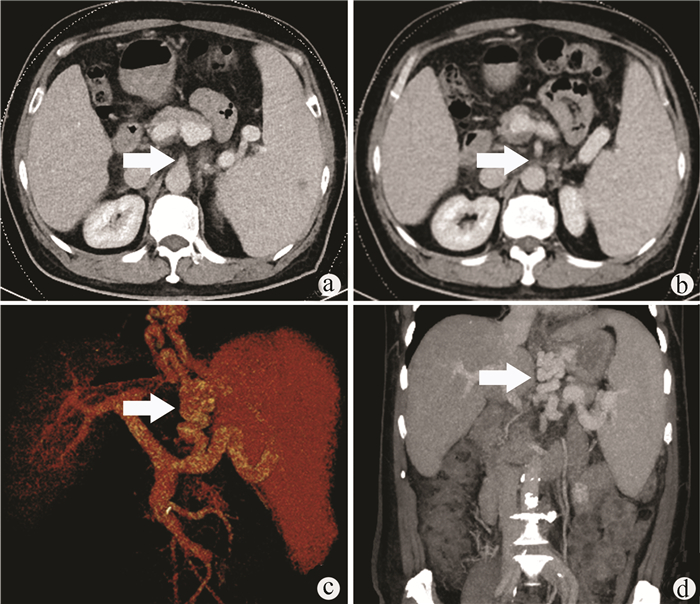

Endoscopic treatment of gastroesophageal varices complicated by posterior reversible encephalopathy syndrome: A case report

Tingting YU, Shanshan JIANG, Mengran ZHU, Yun BAI

2022, 38(1): 177-179. DOI: 10.3969/j.issn.1001-5256.2022.01.030

Abstract(807) HTML (197) PDF (3069KB)(54)

Abstract: